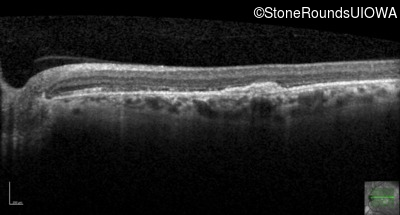

Optical Coherence Tomography - Right - 20/100

Exemplar / OCT Stack